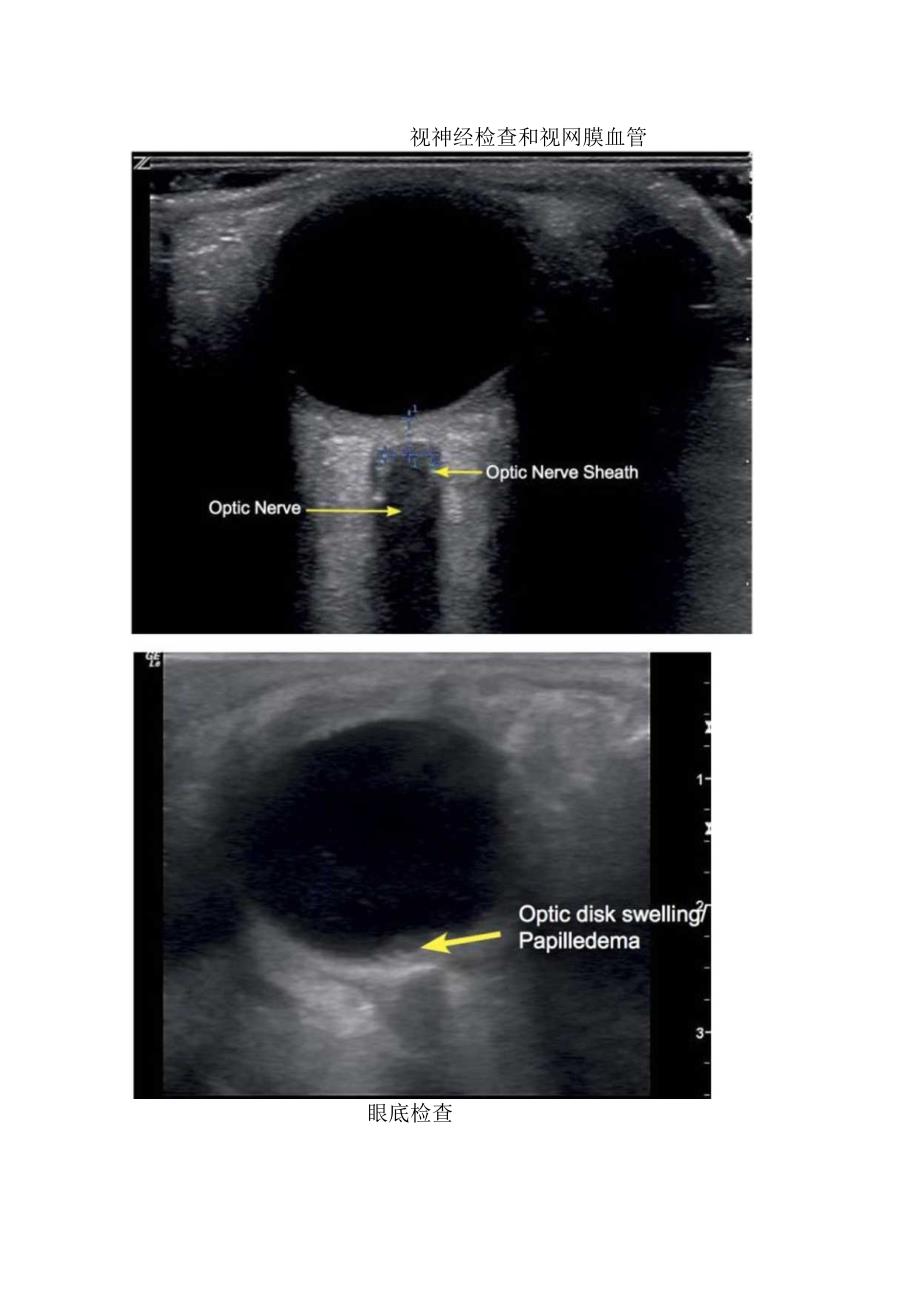

矢状切面、眼底检查等眼部超声检查结构辨认Cornea,眼角膜1.ens,晶状体Choroid/Retina,脉络膜/视网膜Opticdisk,视神经盘OpticNerve,视神经OpticNerveSheath(ONS),视神经鞘AnteriorChamber,前房矢状切面L14-SChoroid&RetinaOpticNerveSheathScleraOpticDiscOpticNerve横断面视神经检查和视网膜血管眼底检查ONDS的测量眼底检查瞳孔检查